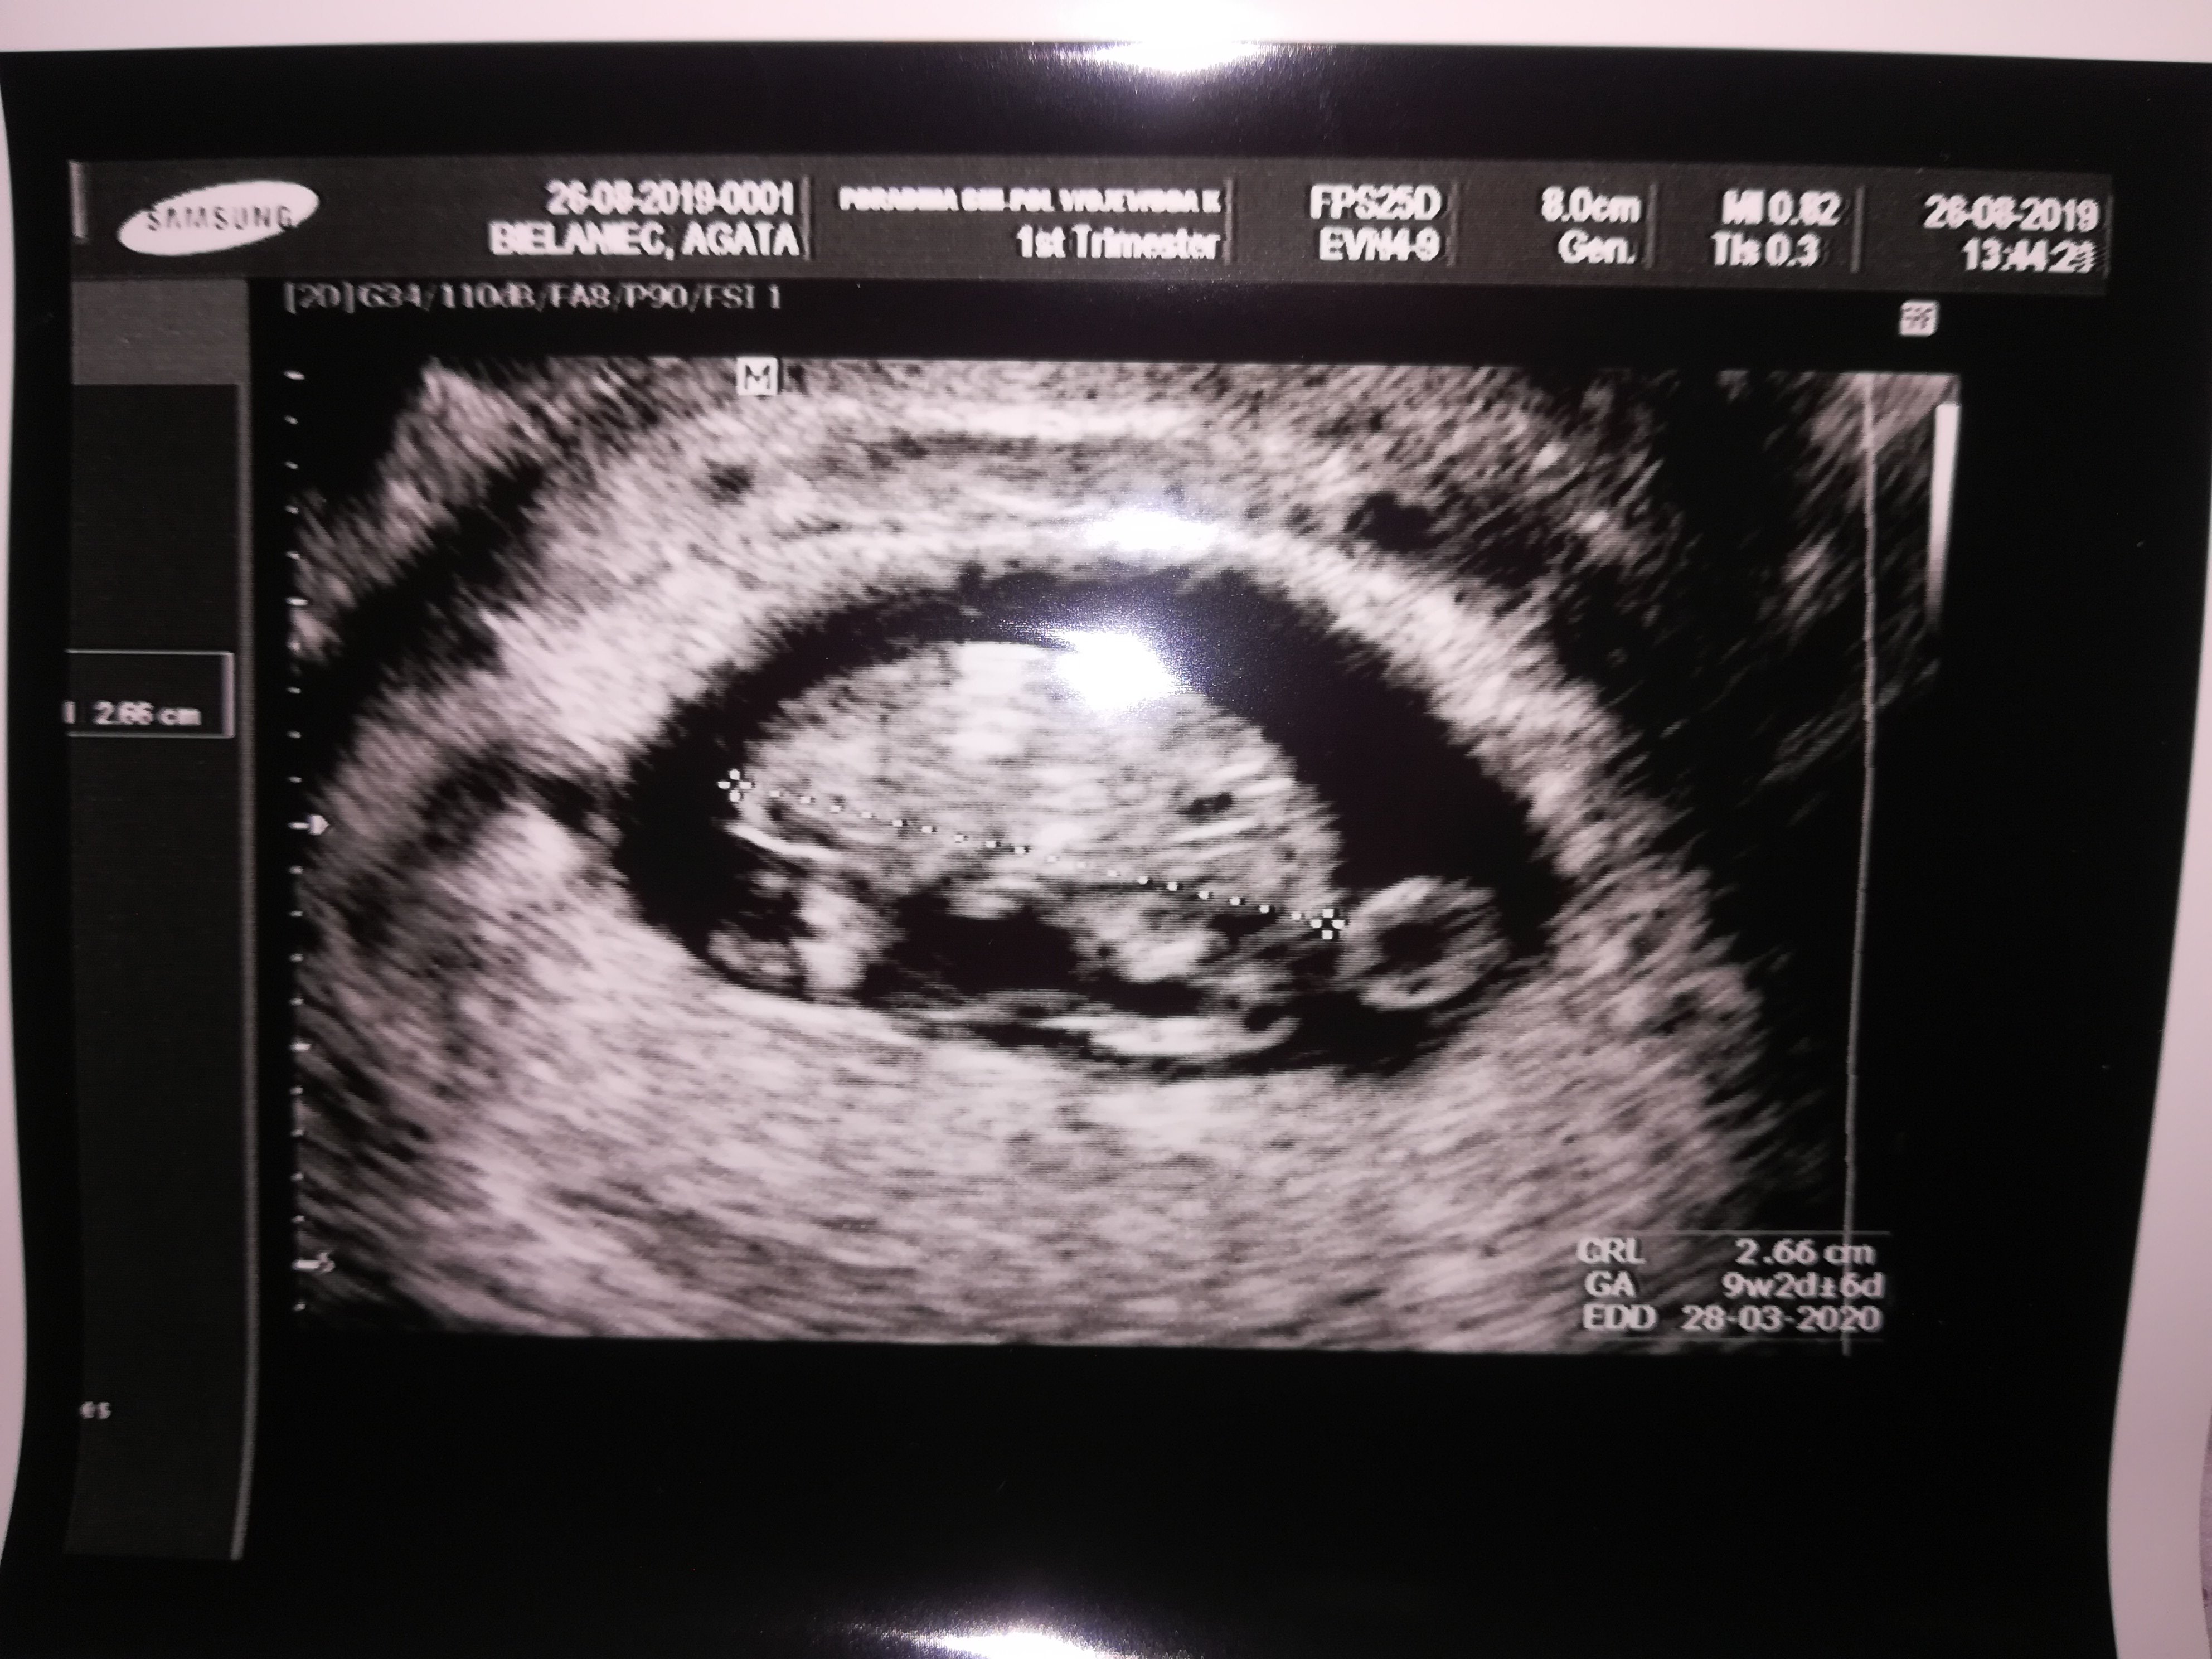

Wszystko ok z maluszkiem 9tydzien2 dzień według usg. Serduszko biło widziałam jak się rusza nie słyszałam powiedział że nie naraża serduszka na te fale że mam przyjść 23 września to będzie 13 tydzień wtedy nagrany na pendrive i wtedy już włączy serduszko ale było widać jak bije.

• IMG_20190826_144241.jpg

IMG_20190826_144241.jpg

1,2 MB · Wyświetleń: 138

Wow, to juz???? Ale piekny zolwik :)